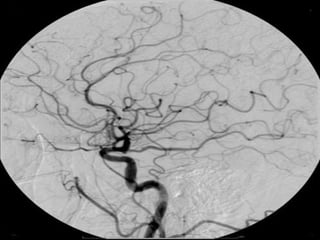

Via renal: administrados de forma intravenosa nos estudos

vasculares (angiografias) tanto de artérias (arteriografia) como de

veias(flebografia) e sistema urinário(urografia intravenosa ou

excretora, cistografia e uretrografia)(*);

Uso de contraste: Uso de contraste:

Flebografia do membro Urografia intravenosa

inferior

Contraste Artificial PositivoIodado Características Se caracteriza por ser hidrossolúvel e facilmente reabsorvido pelo sistema biológico, sendo eliminados por via renal ou via biliar; Via renal: administrados de forma intravenosa nos estudos vasculares (angiografias) tanto de artérias (arteriografia) como de veias(flebografia) e sistema urinário(urografia intravenosa ou excretora, cistografia e uretrografia)(*); Via biliar: estudo da vesícula e vias biliares, sendo administrados por via oral(colecistografia oral) ou por via intravenosa (colangiografia intravenosa); A concentração de iodo no composto influencia na maior ou menor radiopacidade, concentração à 35%, significa 35g de iodo por cada 100ml de diluente. Pode apresentar-se como substância iônica e não iônica.